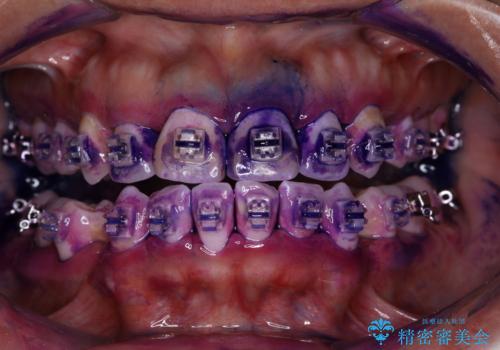

- インビザラインでのマウスピース矯正中の患者様です。

プラークが放置されると、そこで病原菌が繁殖し始めます。そうなるとバイオフィルム(歯面に強固に付着したばい菌の膜)になり、歯肉に炎症が生じ歯周病の引き金となります。

矯正治療中(ワイヤー・マウスピース共に)虫歯や歯周病予防のためには、お口の中を清潔に保つことが大切です。